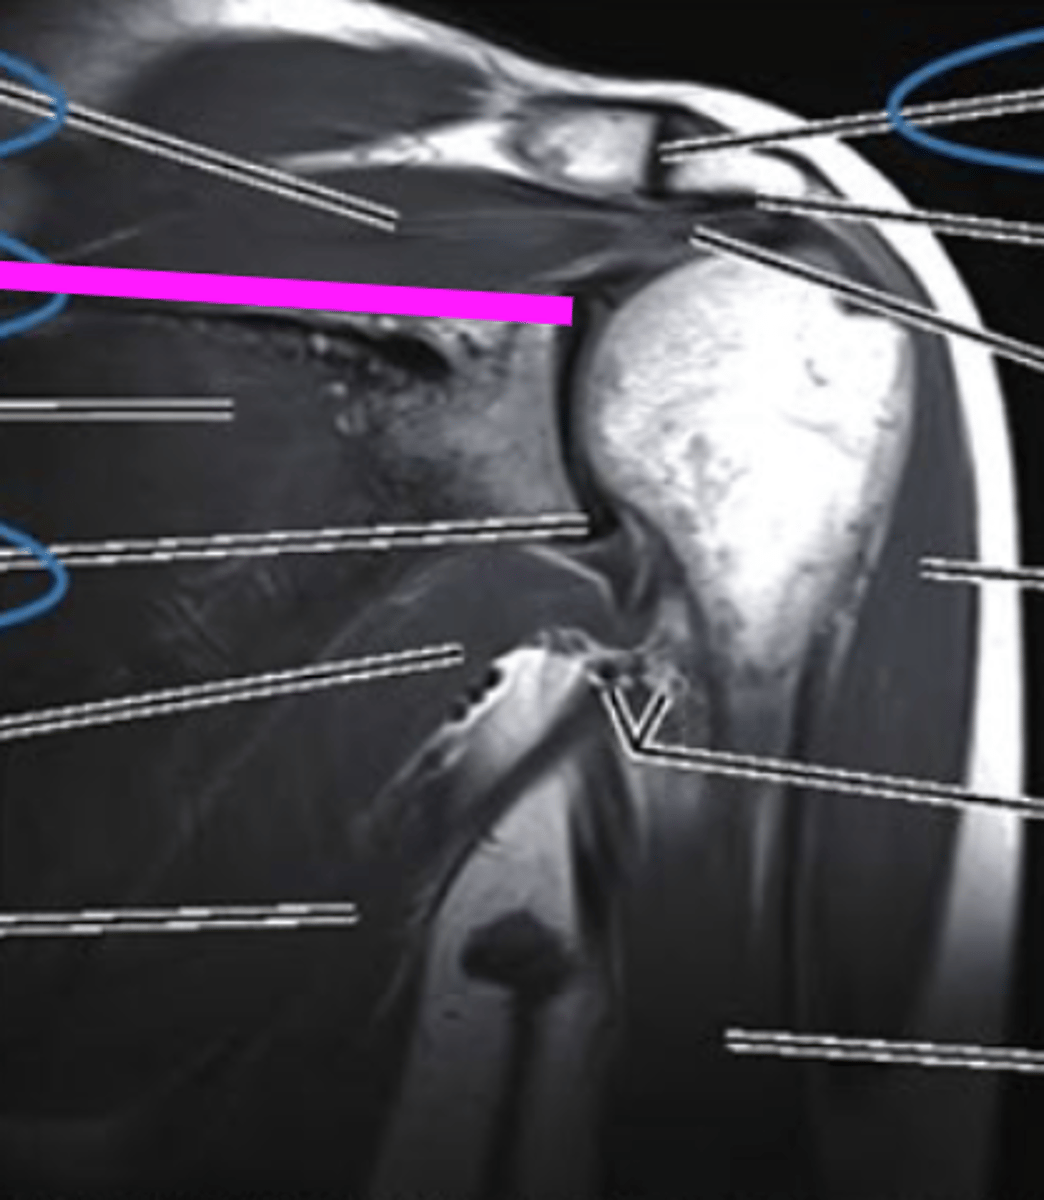

Axial MRI

what imaging type and view is this?

glenoid

what does the pink line point to?

posterior glenoid labrum

anterior glenoid labrum

Humerus